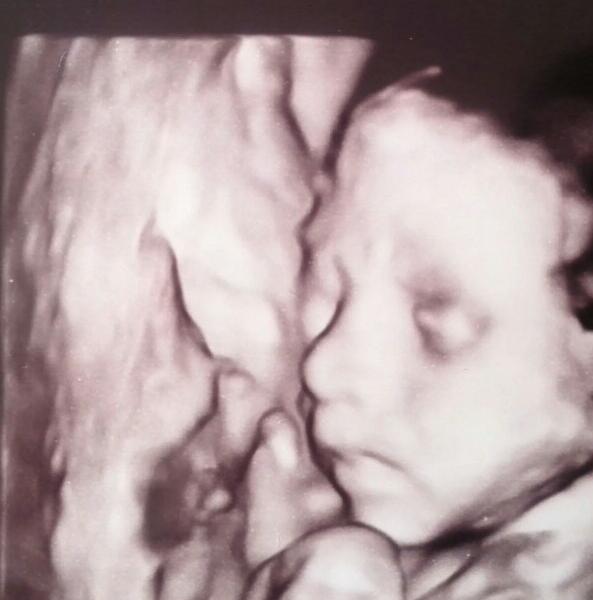

Это мы сегодня))) 25 неделек, 703 гр, активный мальчик. Сказали только, что вод больше, чем нужно (скорее всего из-за перенесенной простуды). Сдала анализы на вирусы, завтра результаты.